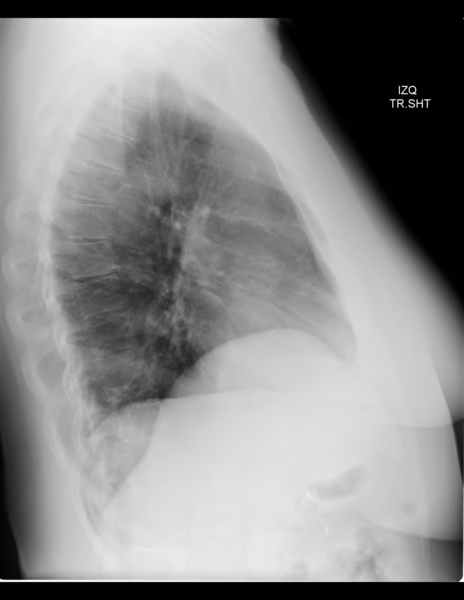

PA Y LATERAL DE TORAX

-Espacio retroesternal con pérdida de su amplitud.

-Llama la atención la elevación del hemidiafragma derecho con diferencia de 5.6 cm.

LA PÉRDIDA DEL ESPACIO RETROESTERNAL PODRÍA CORRESPONDER A AUMENTO DEL TAMAÑO DEL VENTRÍCULO DERECHO VS ORIGEN A DETERMINAR.